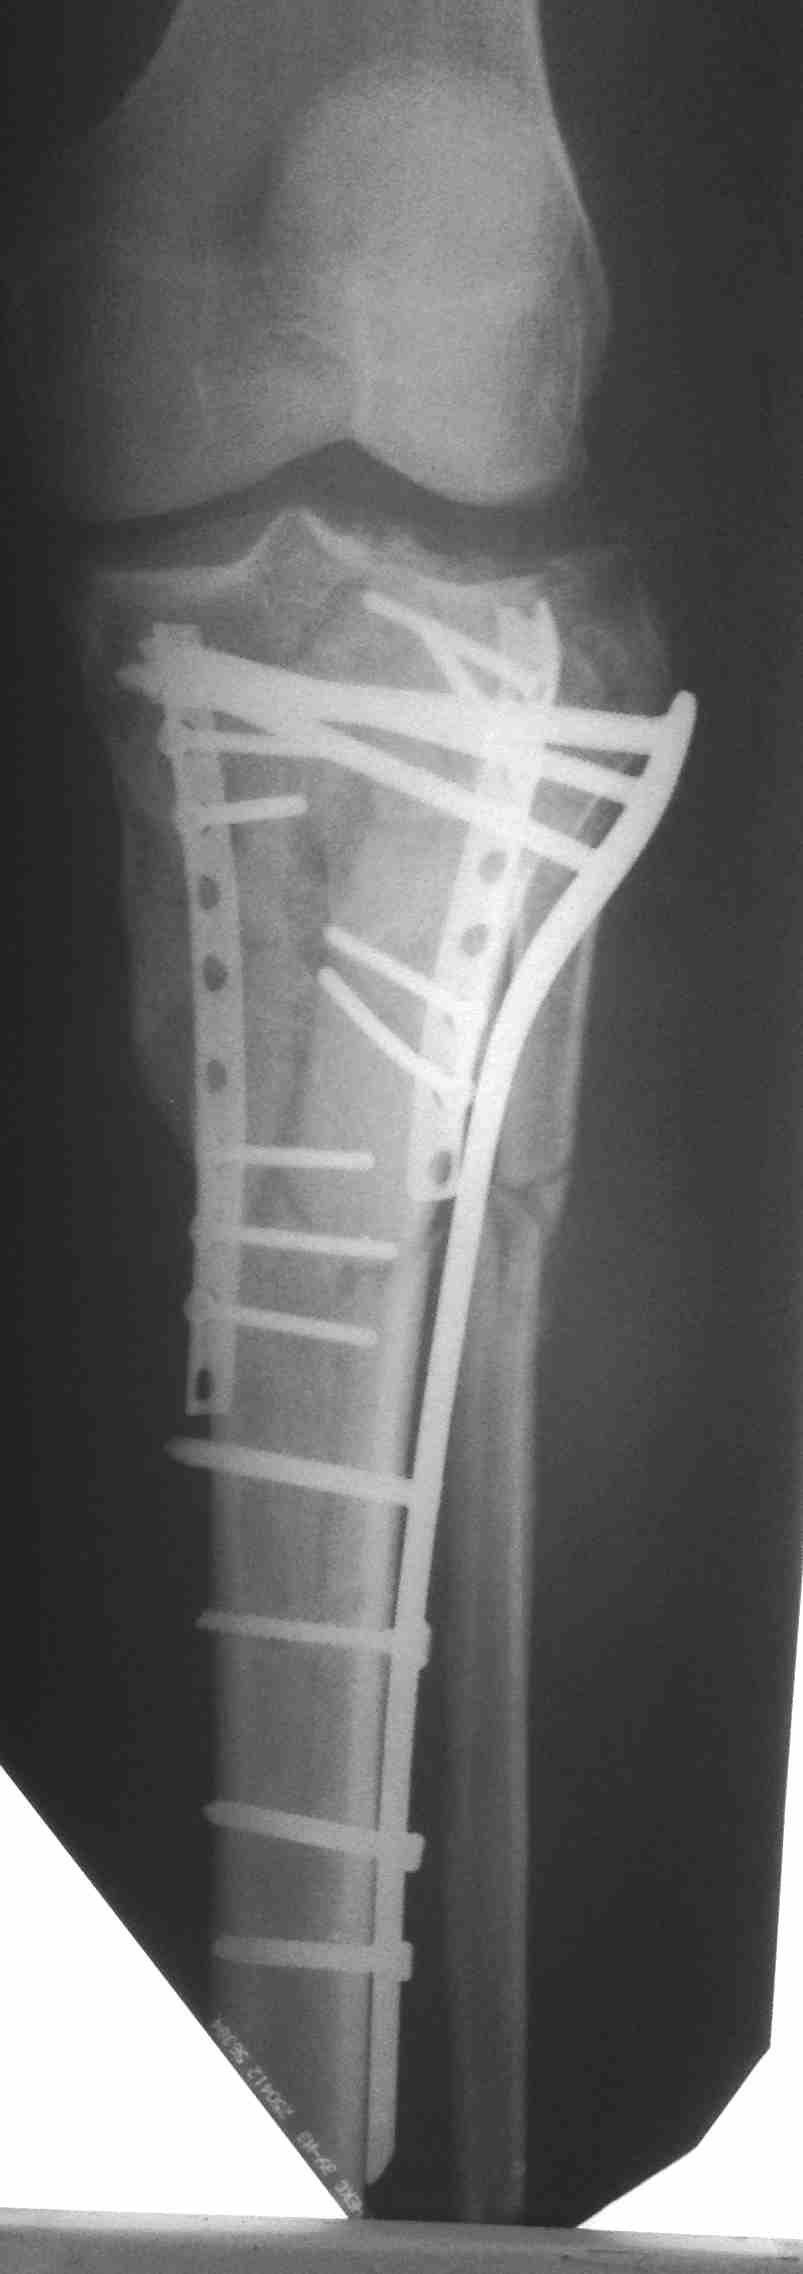

перелом мыщелков голени и вывих бедра (результат операции)

продолжение темы http://weborto.net/forum/1435828753

Кожа пришла в норму только к полутора месяцам, операция из двух доступов.